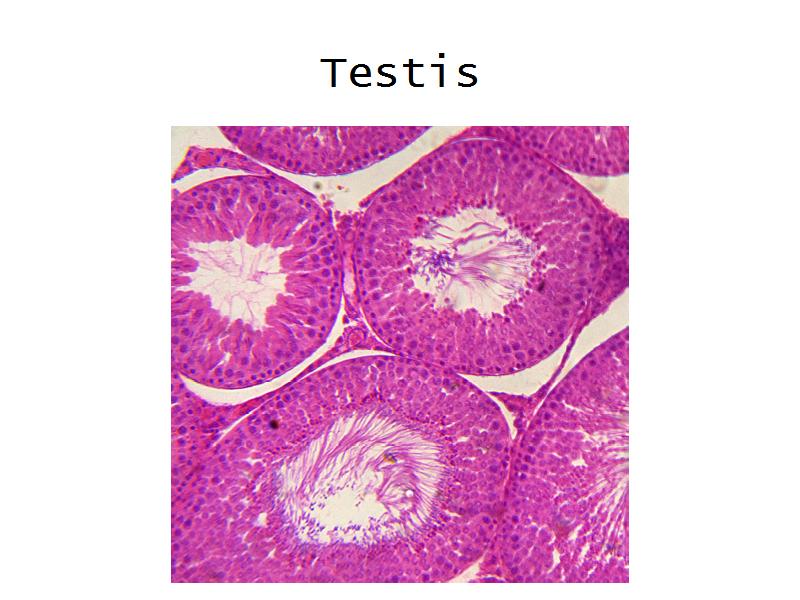

- Testis

- C2: Testis

- C2: Testis = testosterone

- D1: Leydig cells

- D1: Leydig cells = testosterone

- Slide 84: Testis